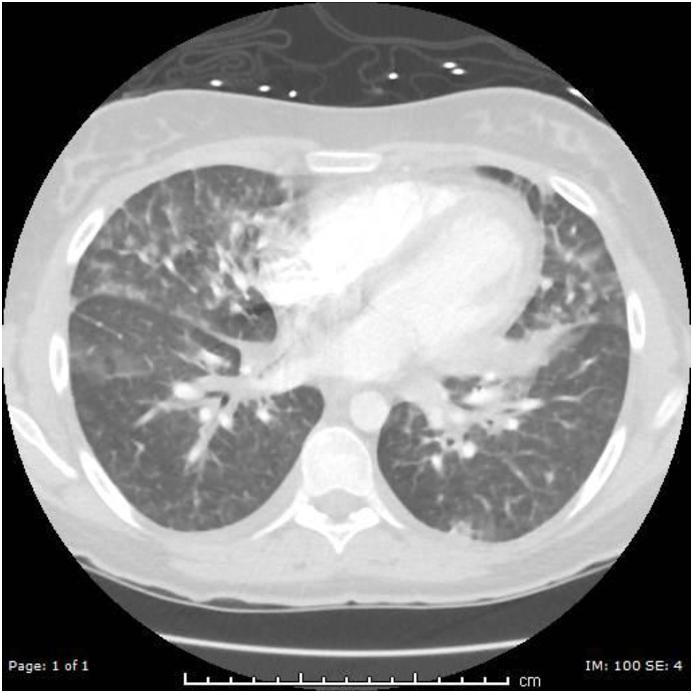

Electronic cigarette (e-cigarette) use, or vaping, is gaining widespread popularity among adults aged 18-35. Vaping is commercially promoted as a safer alternative to traditional cigarette smoking. Previous studies have reported a close relationship between conventional cigarette smoking and acute eosinophilic pneumonia (AEP), but only one case report to date associates vaping with AEP in a male patient. We present the first case of AEP involving a young female after use of e-cigarettes. Clinicians should consider AEP when evaluating young patients with hypoxic respiratory failure and a recent history of e-cigarette use. This case highlights the need for more research into the relationship between e-cigarettes and AEP.

电子烟的使用,即吸电子烟,在18至35岁的成年人中越来越普遍。电子烟在商业上被宣传为比传统吸烟更安全的替代品。先前的研究报告了传统吸烟与急性嗜酸性粒细胞性肺炎(AEP)之间的密切关系,但迄今为止只有一例病例报告将吸电子烟与一名男性患者的AEP联系起来。我们报告了首例在使用电子烟后发生AEP的年轻女性病例。临床医生在评估患有低氧性呼吸衰竭且近期有吸电子烟史的年轻患者时应考虑AEP。该病例凸显了对电子烟与AEP之间关系进行更多研究的必要性。